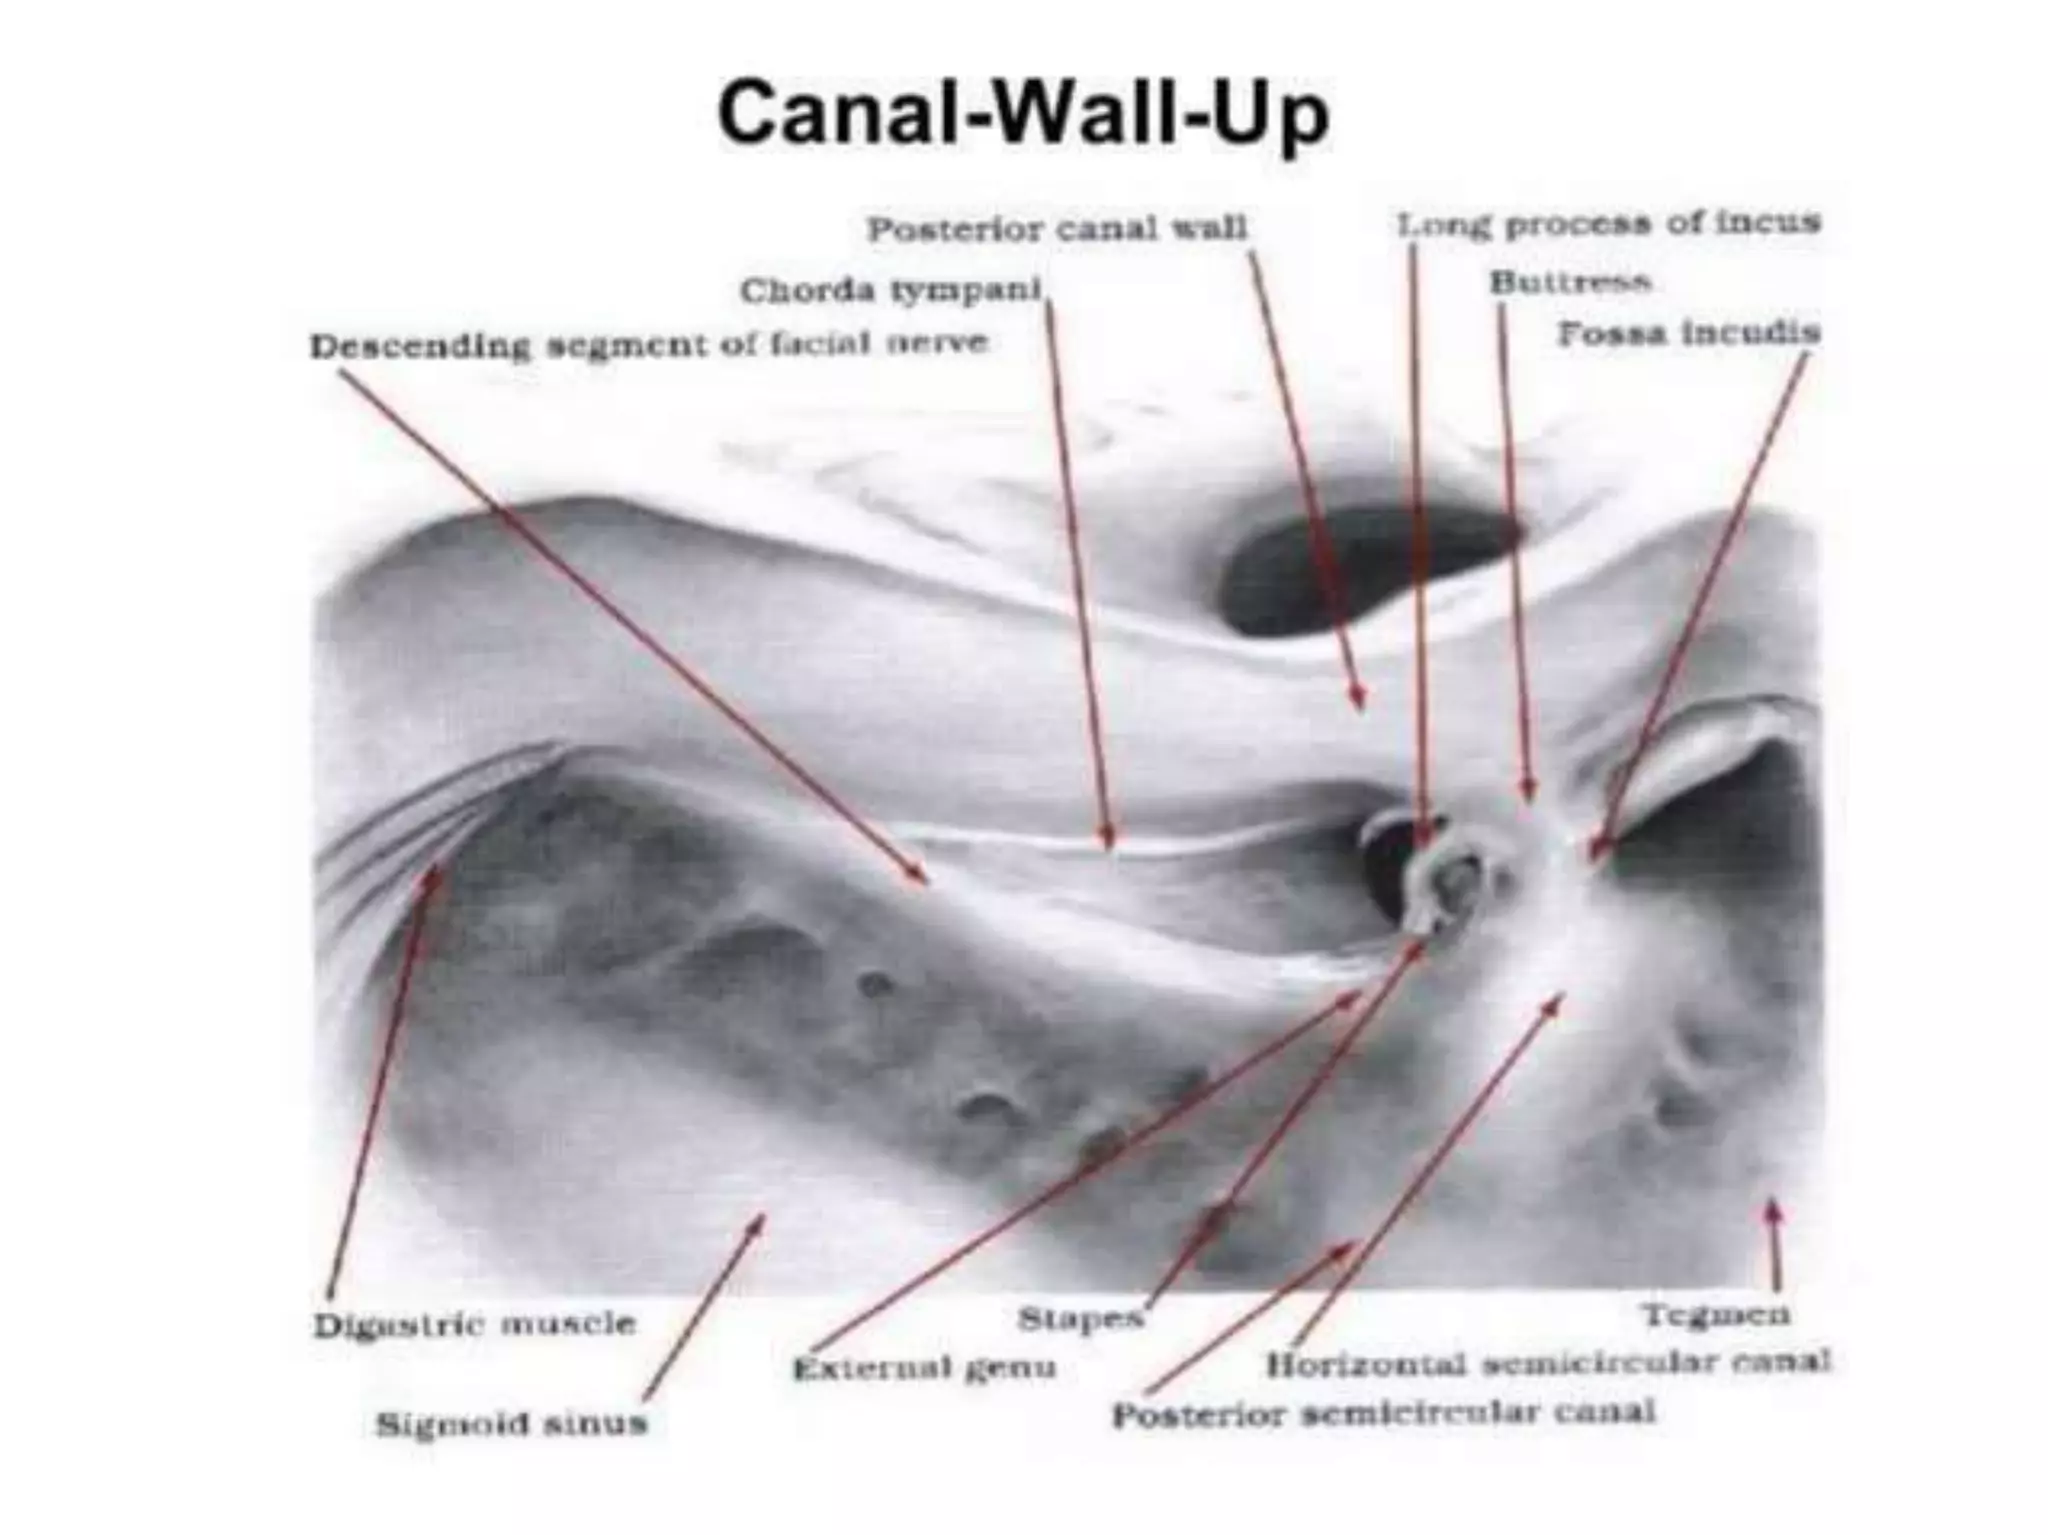

Chronic otitis media is a chronic inflammation of the middle ear and mastoid cavity that presents with recurrent ear discharge through a perforated eardrum. It has several subtypes depending on the state of the eardrum perforation and epithelium. It can be caused by prior acute otitis media, genetics, environment, eustachian tube issues, gastroesophageal reflux disease, craniofacial abnormalities, or immune deficiency.